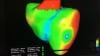

This is a virtual heart with the same electrophysiology characteristics as the real patient unveiled by Siemens at the Healthcare Information Management and Systems Society (HIMSS) 2019 annual meeting in February. This "digital twin" technology is in development and will be able to create virtual, digital organs from a patient’s medical imnaging and other physiological data. In this case, the model was created using an ECG, MRI scan and other clinical data. It was shown as a way to help optimize cardiac resynchronization therapy (CRT) lead placement. CRT currently has a 30 percent nonresponder rate, which is mainly due to the placement of leads. This model allows virtual placement of the leads In various locations to test response prior to the implantation procedure. The green dot shows the location of the virtual lead. Siemens said the technology also might have applications for testing virtual ablations strategies to save procedure time when the patient is in the EP lab.